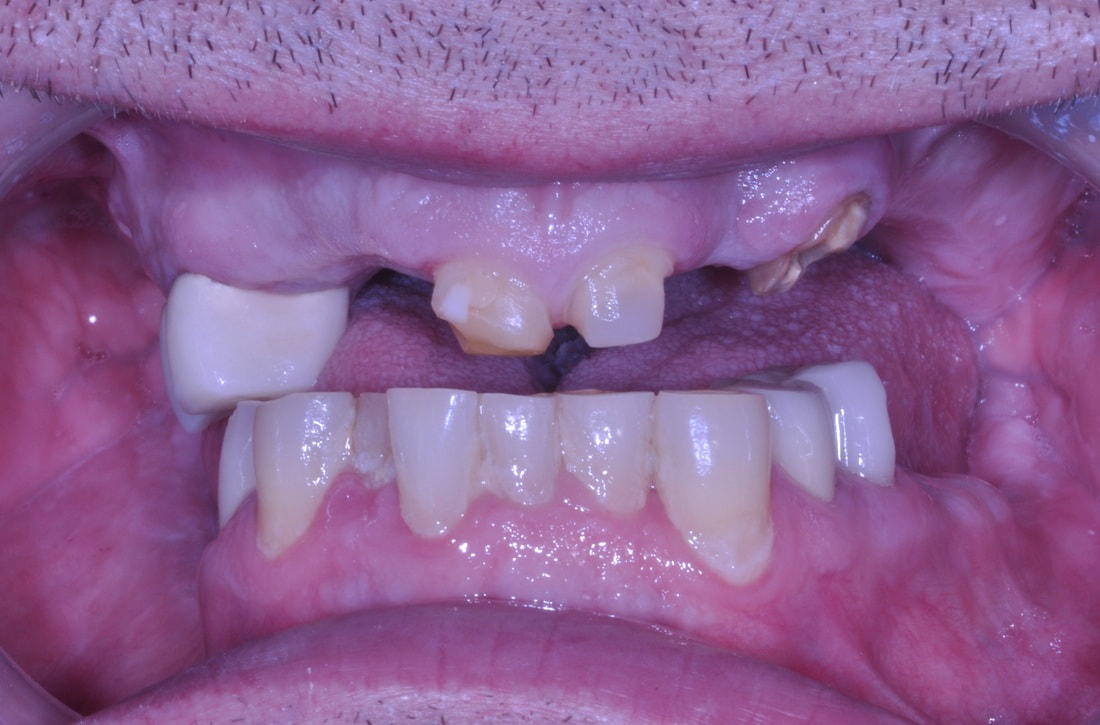

FULL MOUTH RECONSTRUCTION

This is one of the most difficult, so called “multidisciplinary” cases.

Wide spectrum of dental techniques and clinical procedures was used during this complex dental therapy. Among those were the following:

- Neuromuscular Diagnosis and Treatment of TMD-TMJ

- Dental Implants, Bone grafts & Sinus Lifts

- CAD/CAM Digital Restorative Dentistry

- Cosmetic All-ceramic Veneers, Crowns and Dental Bridges

- Teeth Extractions

- Laser Dentistry, Digital X-Rays, Virtual Smile Design

- Bio-mimetic Dentistry